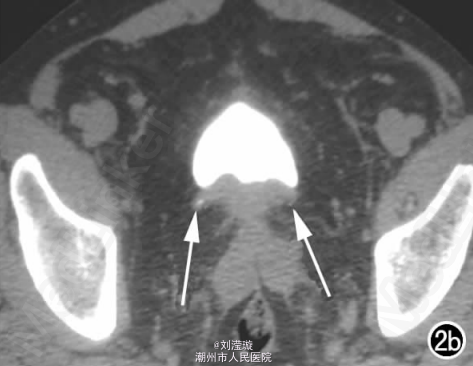

腹部B超示双肾增大,双肾慢性肾病声像;双肾中度积液伴双输尿管上段扩张。 IVPshi双侧输尿管中或下段梗阻。 膀胱造影:经尿道置管后,注射对比剂充盈膀胱,膀胱下半部先充盈,继续灌注对比剂后见膀胱完全显影,膀胱形态异常,呈“倒葫芦状”(图1)。 CT增强扫描行延迟期 MPR重组,见双侧肾盂、肾盏扩张积液;双侧输尿管纡曲、扩张,下端呈鸟嘴样变窄;膀胱变形、体积减小(图2); MRI平扫示双侧肾盂、肾盏扩张积液,双侧输尿管扩张并下端鸟嘴样变窄,盆腔内多量脂肪沉积,分布于膀胱、直肠周围,T1WI、T2WI呈明显高信号,T2WI抑脂像呈稍高信号,膀胱受压变形、体积减小(图3a~c); MRU示双侧肾盂肾盏扩张、积液,双侧输尿管显著纡曲、扩张,下端鸟嘴样变窄,管壁光整,膀胱变形、体积较小、位置抬高(图3d)。